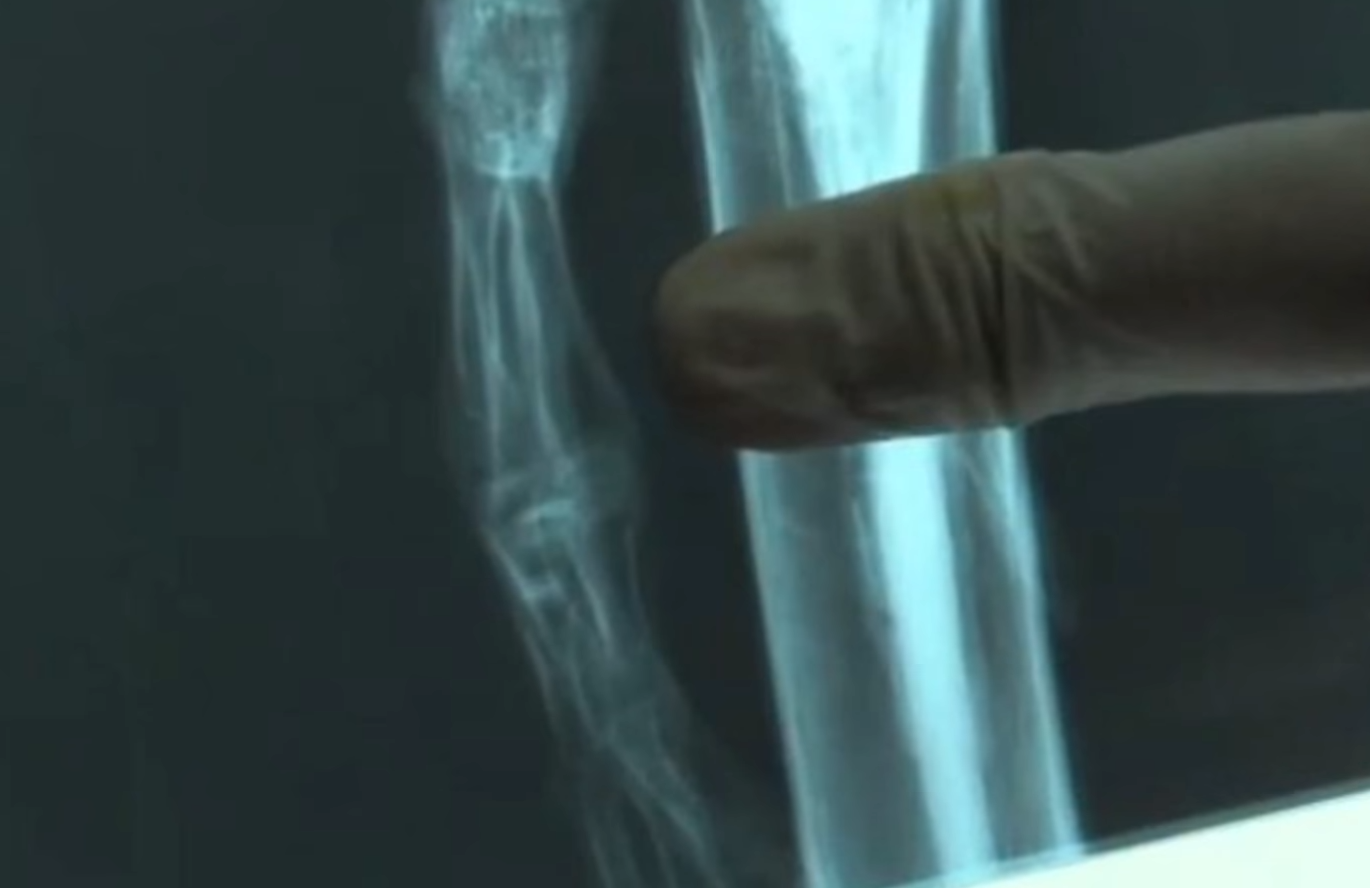

Кроме того, у нее всего десять пар ребер (в отличие от двенадцати обычных для человека), а ее кости - слишком "зрелые" (на это указывает их плотность и форма).

На подробное изучение Аты в калифорнийском Стэнфордском университете ушло около полугода. Анализ ДНК, взятый из костного мозга ребер, показал, что мумия представляет собой редкую мутацию человека женского пола, или неизвестную ранее аномалию развития скелета.